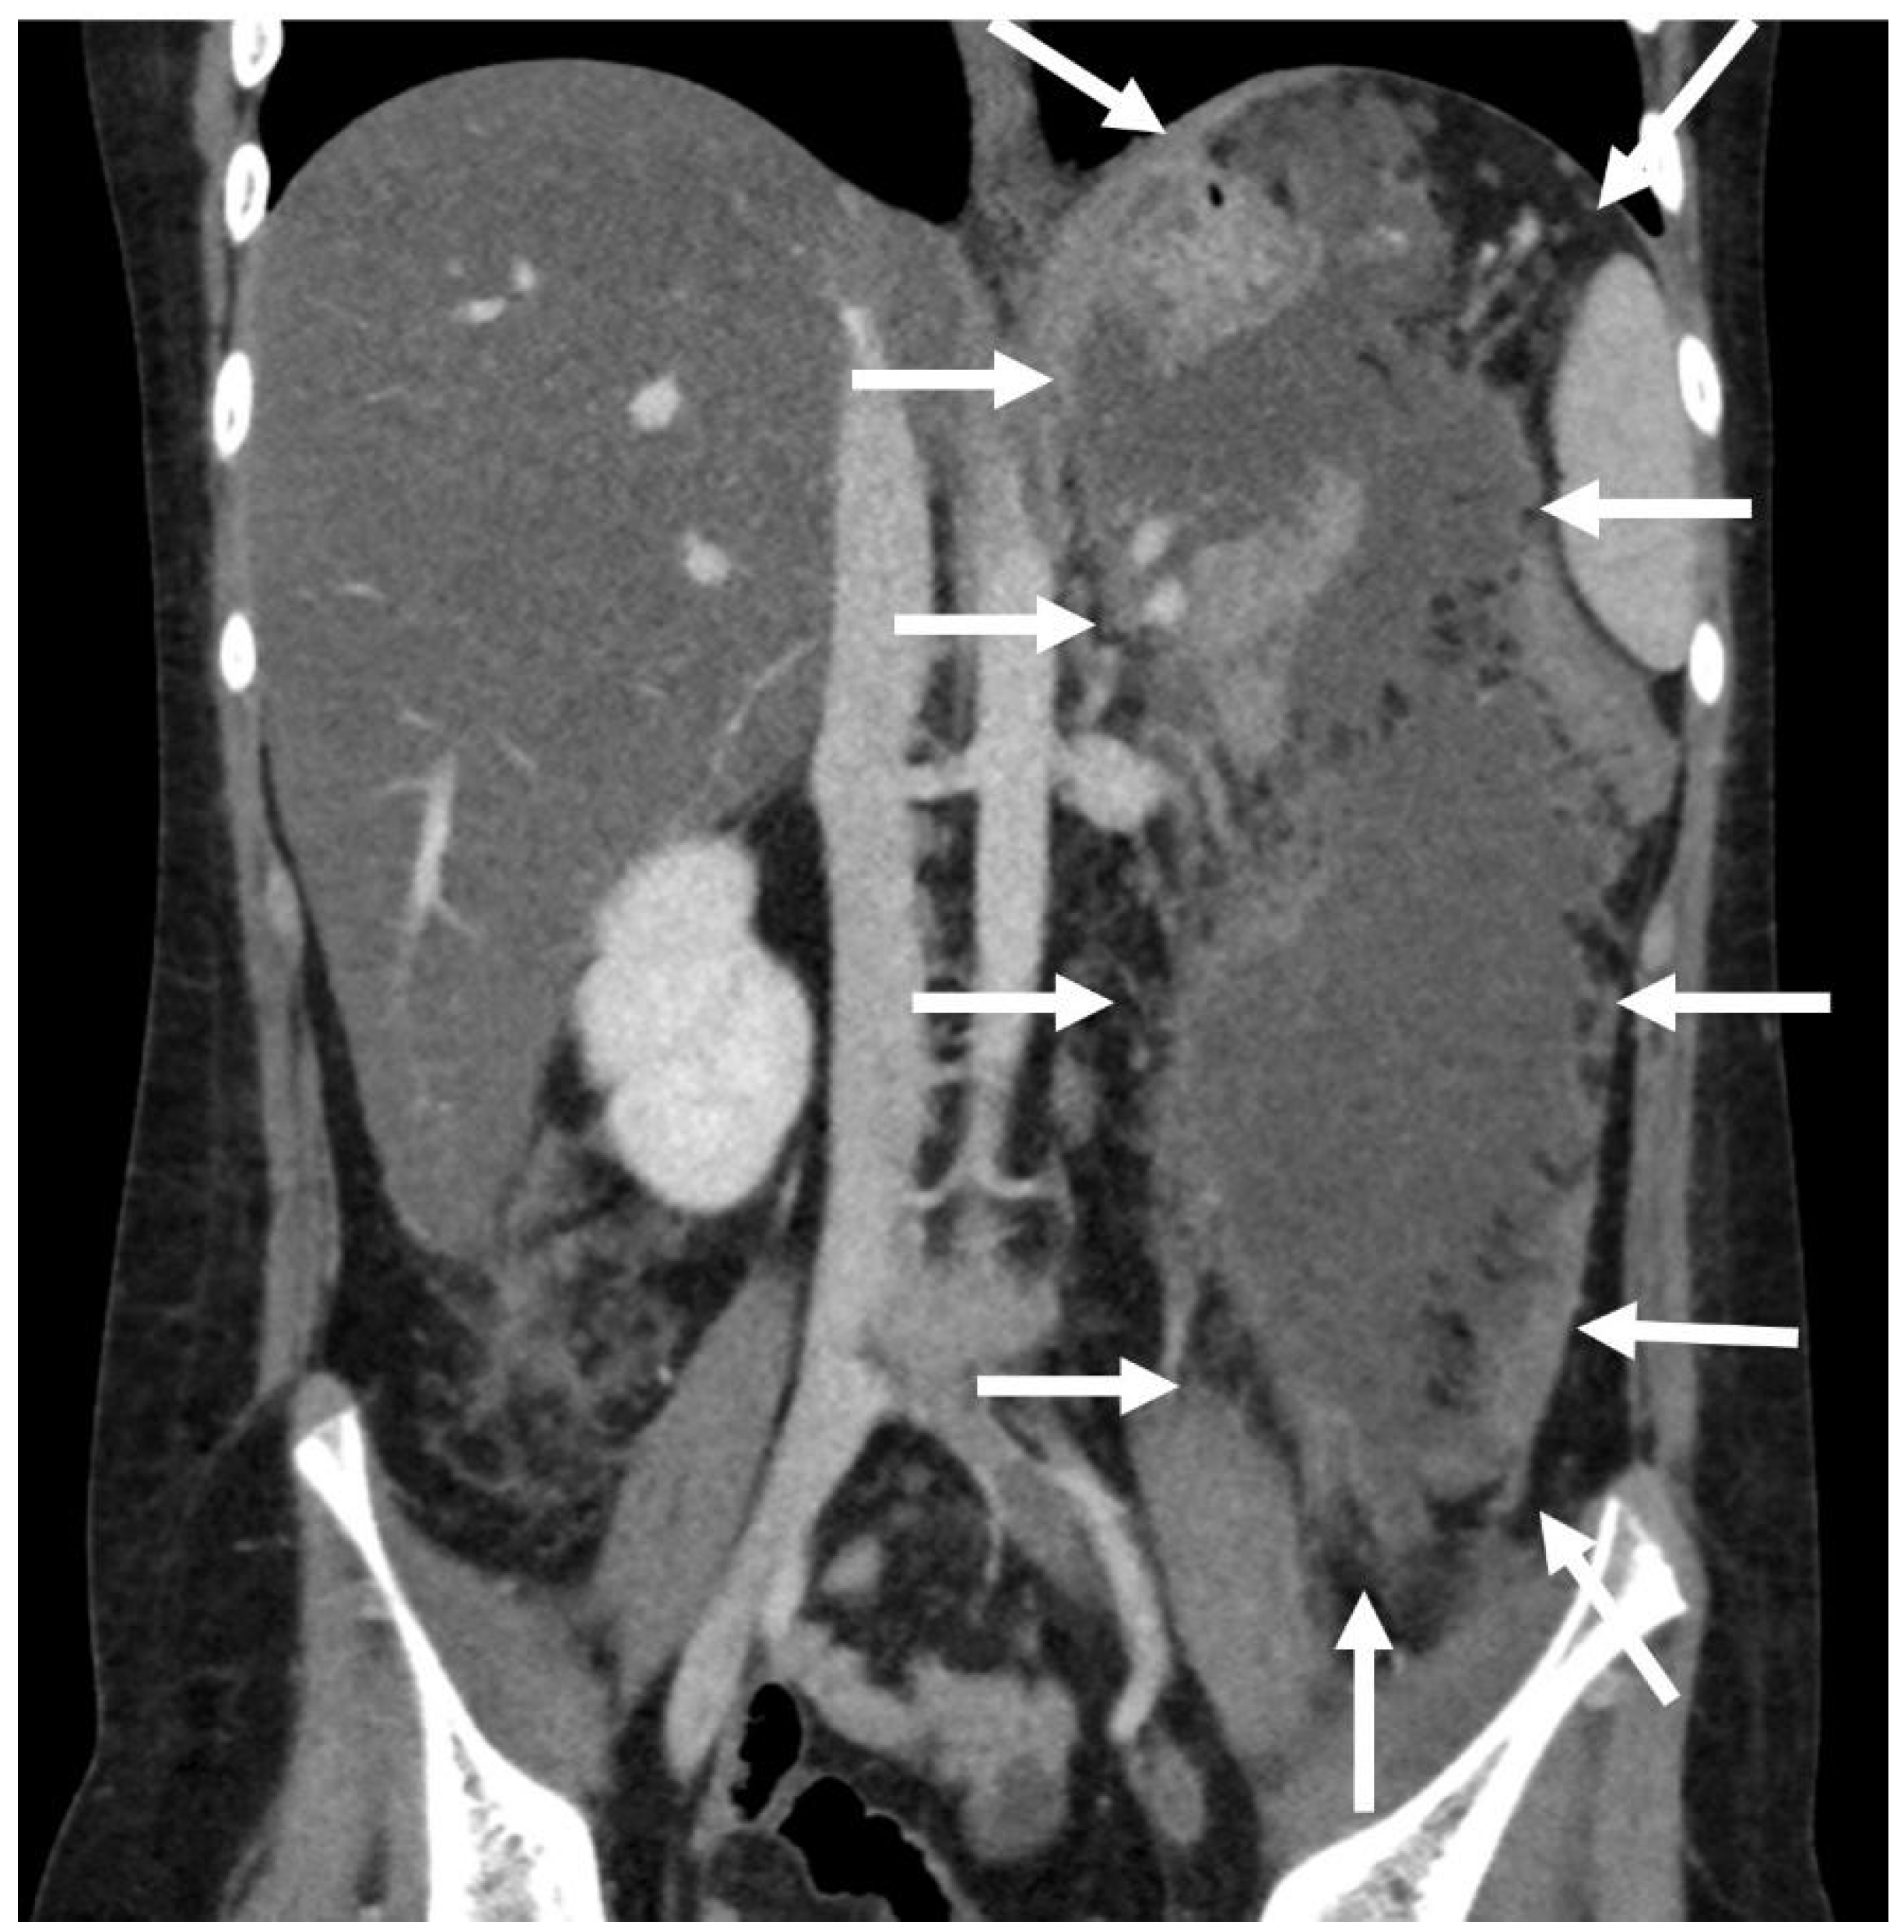

3.1.3. Patient n°3

A 10-year boy affected by T-lymphoblastic lymphoma developed a WON after chemotherapy-induced necrotic-hemorrhagic pancreatitis, with fever, vomit and abdominal pain. Clinical conditions were also complicated by deep vein thrombosis involving the left femoral vein and inferior vena cava. Abdominal CT showed a large WON, with a major diameter more than 22 cm (Figure 5). Considering the worsening of clinical condition and the need to an early resume of the chemotherapy, he underwent a primary EUS-guided cystogastrostomy and EC-LAMS positioning; we did not perform necrosectomy. Post-operative course was uneventful. MRI performed 37 days after the procedure, showed a significant reduction of the WON (Figure 6); subsequent US images were performed for follow-up, until the WON was no more visible. Endoscopic removal of the device was performed 48 days after cystogastrostomy.

Figure 5.

Patient n°3 CT. Necrotic-hemorrhagic pancreatitis (body/tail origin) with voluminous walled-off necrosis developing in the left quadrant (hypochondrium/flank; relations to stomach, spleen, kidney, descending colon), extending craniocaudal about 22 cm.

Figure 6.

Patient n°3 MRI. Reduction of the walled-off necrosis; the device is in place (in the white circle).

Patient is still undergoing oncologic therapy, but at one-year follow-up he has had no recurrence of acute pancreatitis and PFCs.